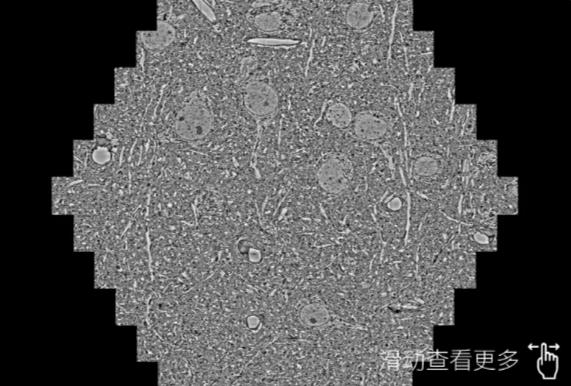

鼠脑切片。左图使用九龙坡蔡司九龙坡扫描电镜MultiSEM706对165μmx143pm面积区域成像,耗时仅需1.5秒。右图为鼠脑切片中30μm区域放大效果。样品由芝加哥大学B.Kasthuri提供。

使用蔡司高速九龙坡扫描电镜MultiSEM对1mm²人脑皮层组织进行高分辨成像,并对其中的各种细胞结构进行三维重构分析。左图展示了2x3mm²组织平面中锥体神经元的三维重构效果。右图显示了局部体积神经元三维重构。图像由哈佛大学chtman实验室提供,渲染图由D. Berger 制作。